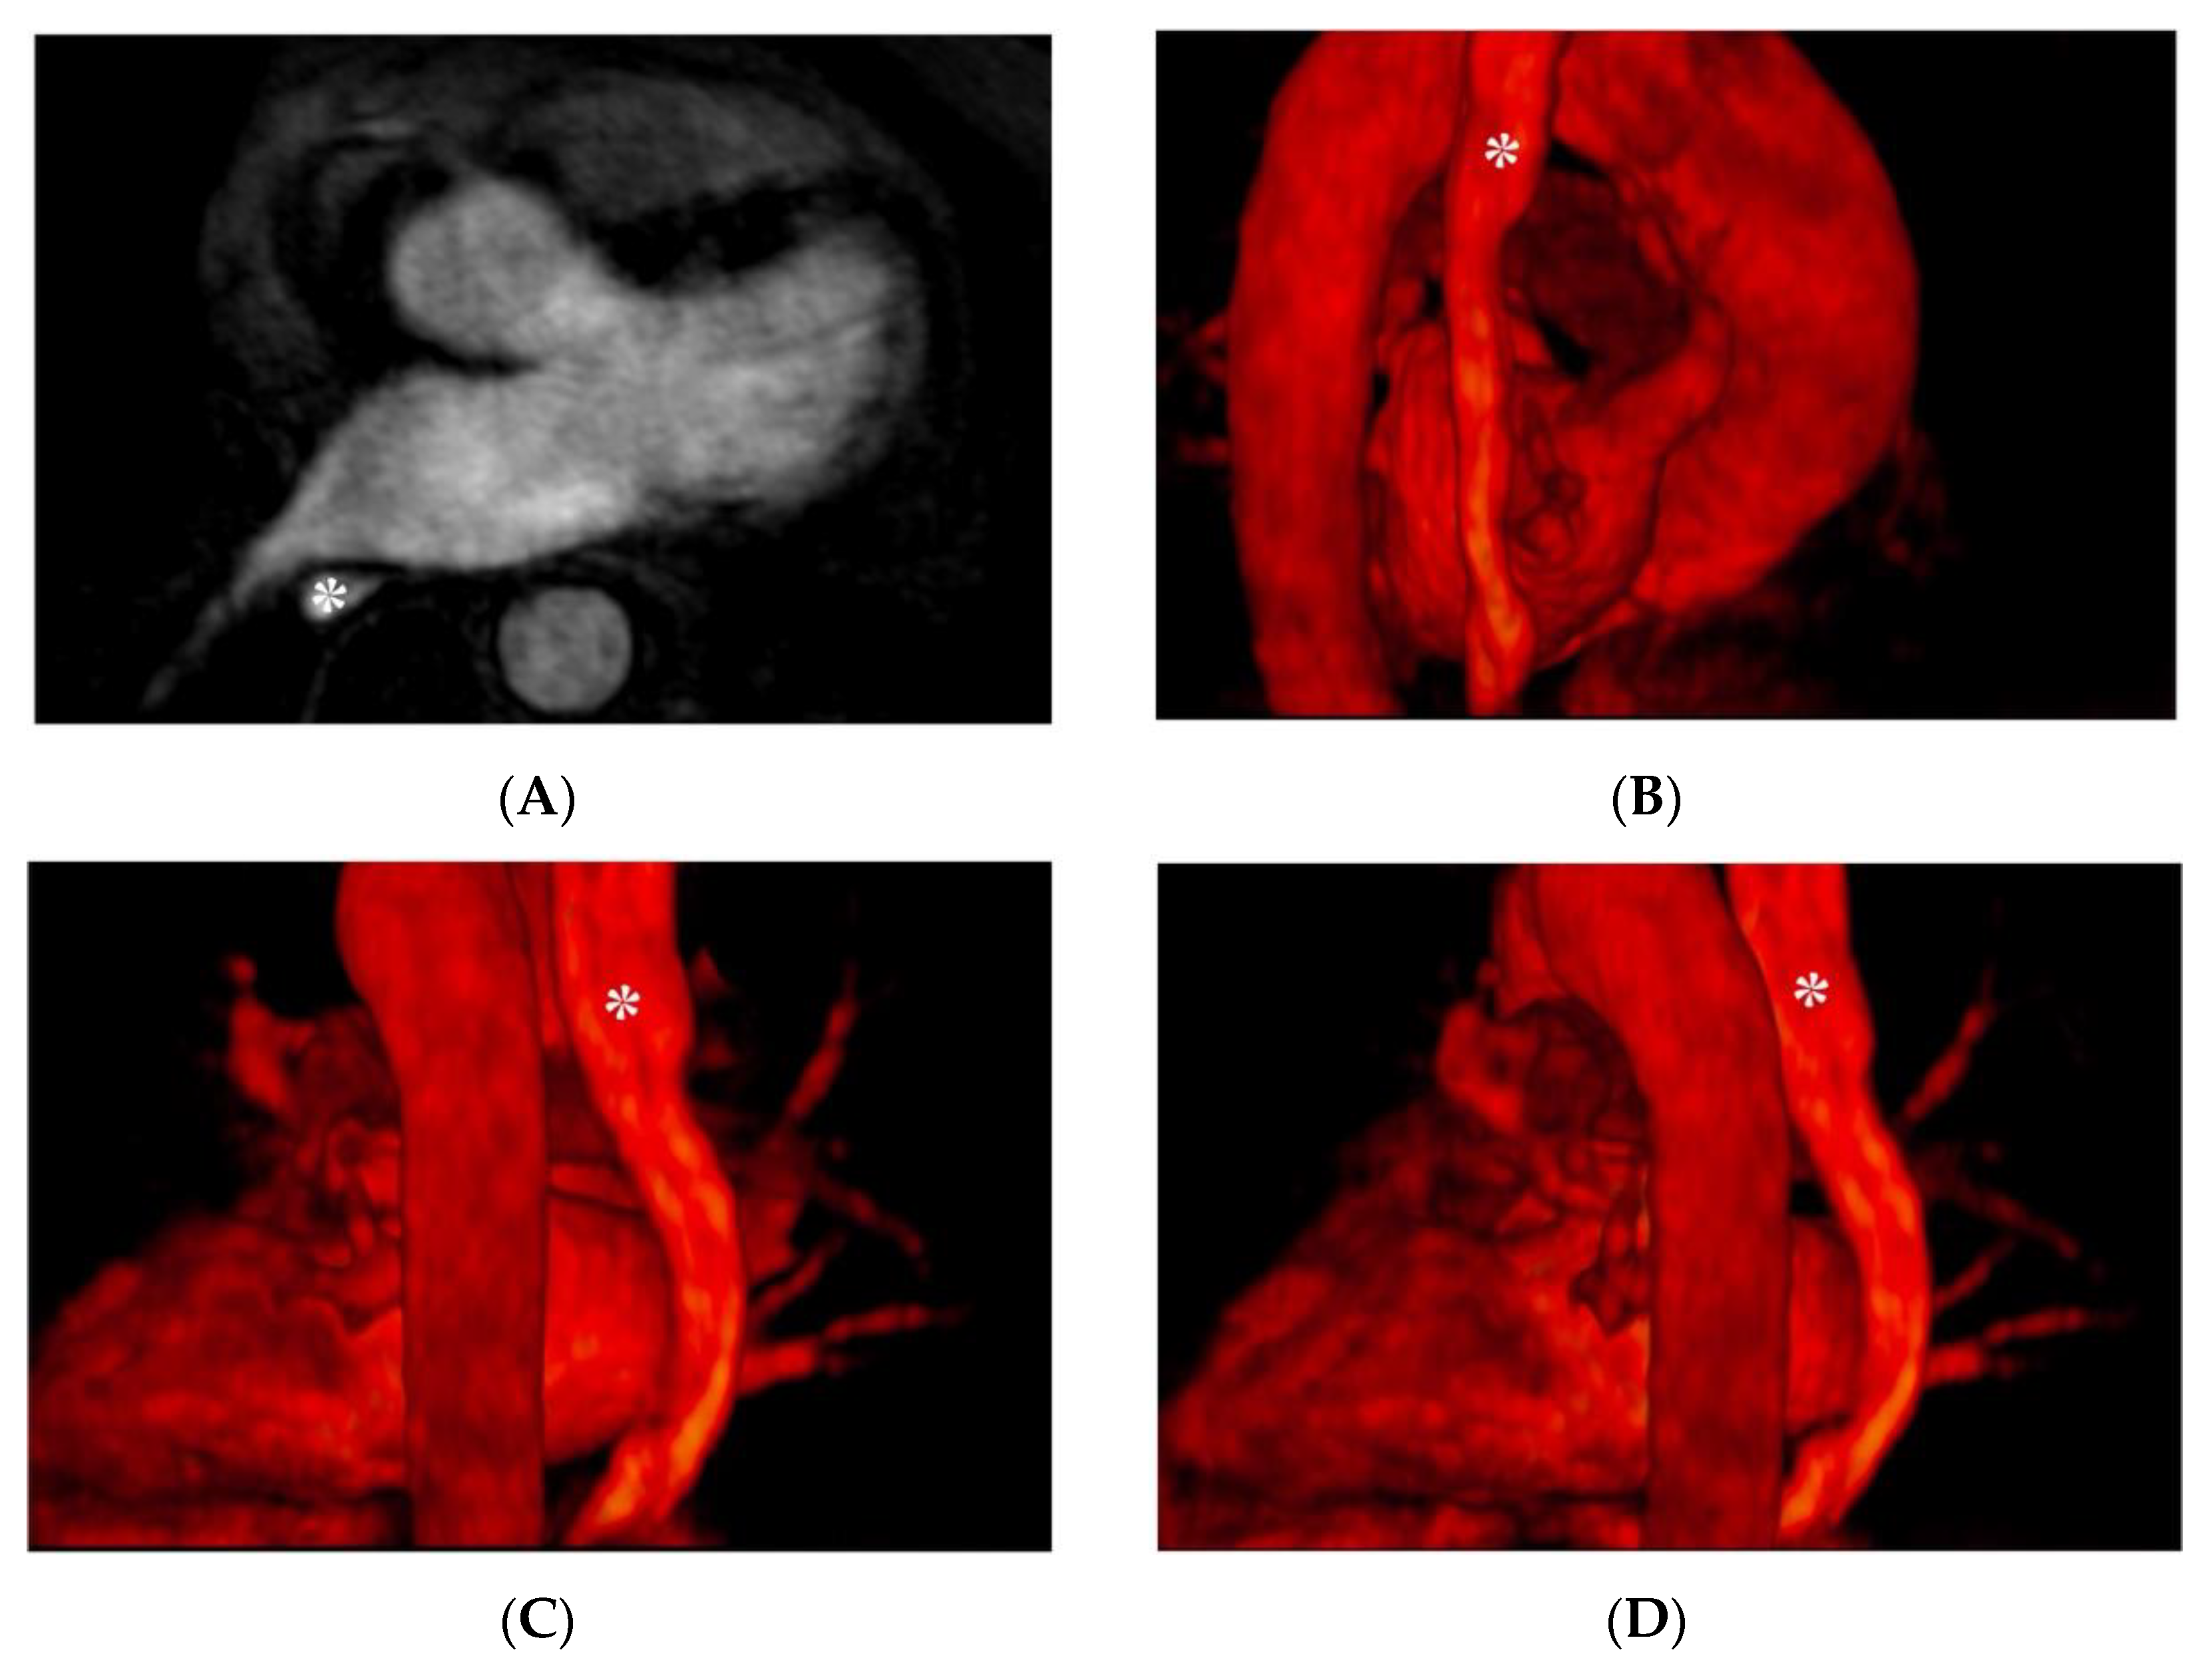

3.5. Atrial Thrombus Assessment

- Kitkungvan, D.; Nabi, F.; Ghosn, M.G.; Dave, A.S.; Quinones, M.; Zoghbi, W.A.; Valderrabano, M.; Shah, D.J. Detection of LA and LAA Thrombus by CMR in Patients Referred for Pulmonary Vein Isolation. JACC Cardiovasc. Imaging 2016, 9, 809–818. [Google Scholar] [CrossRef]